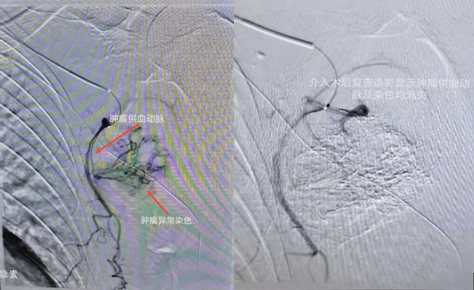

介入術(shù)中圖片

近日,吉林國文醫(yī)院淋巴瘤科與介入一科相互合作,成功為一例皮膚惡性黑色素瘤患者,實(shí)施了實(shí)體腫瘤動(dòng)脈灌注化療栓塞術(shù),患者李某某10個(gè)月前曾確診為皮膚惡性黑色素瘤,腫瘤分布在左側(cè)腋下,患者既往曾多次行靜脈化療及免疫治療,但腫瘤病情仍然繼續(xù)進(jìn)展,患者目前左側(cè)腋下腫瘤病灶增長較快,伴有局部脹痛感,淋巴瘤科左淑波主任綜合分析患者病情后,邀請(qǐng)介入一科韓長清主任進(jìn)行共同商討治療方案,評(píng)估是否可行介入手術(shù)治療,經(jīng)兩位主任共同商討后決定,可給予患者行腫瘤供血?jiǎng)用}化療栓塞術(shù)介入治療。介入術(shù)中非常順利,成功尋找到腫瘤供血?jiǎng)用}并給予治療,術(shù)后患者恢復(fù)良好,疼痛癥狀有所改善。